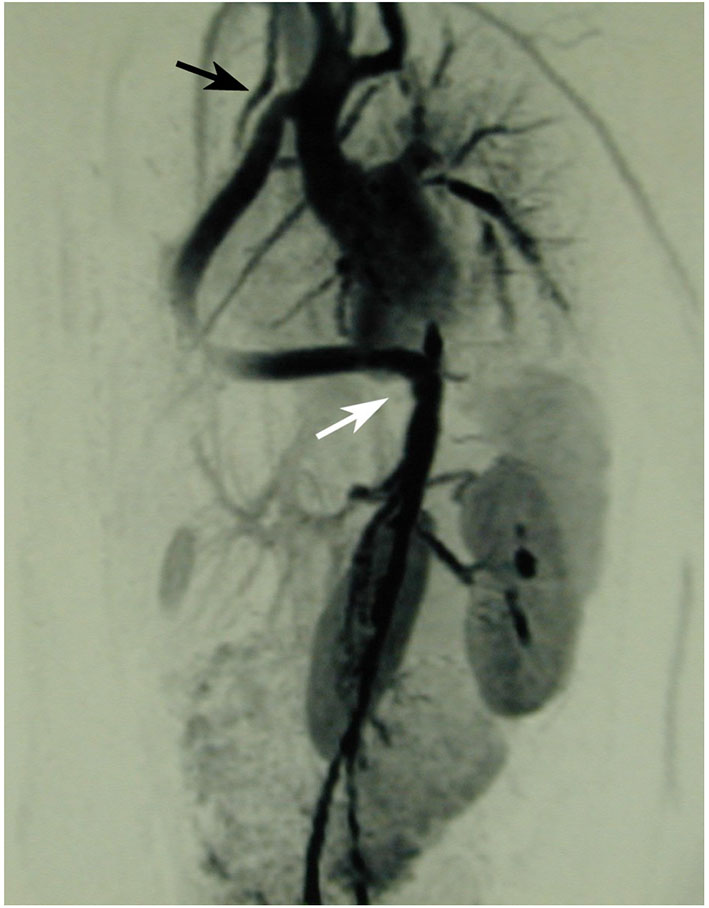

The first patient is a 15–20 year-old female who suffered from increasing claudication symptoms that appeared after a walking distance of <50–100 meters. Suspicion of Takayasu arteriitis was made in the past and clinical examination revealed arterial hypertension of the upper extremities but no pulse at the femoral arteries and distally of them. CT-scan with angiography showed several narrowing at the level of the descending thoracic but also of the abdominal aorta (Figure 13 both left). Since the contrast agent seemed to stop at the level of the external iliac arteries, a direct angiography was planned but the catheter could not be introduced, neither into the radial nor into the femoral arteries for selective injections. At that stage we recommended an extra-anatomic (subcutaneous) thoraco-bifemoral bifurcated graft and this procedure will be performed as soon as possible.

Figure 13

Left (2 pictures): CT-angiogram of a young patient with Takayasu aortitis with multiple stenoses in the thoracic and abdominal aorta and occlusion of the iliac arteries scheduled for an descending to bi-iliac extra-anatomic bypass. Right (2 pictures): CT-angiogram of a 45 yr-old female with severe calcific narrowing of the descending aorta as a result of a Takayasu more than 25 years before. Endovascular procedure was thought to be not ideal in this case.

The second patient is a 45-year old female known for a Takayasu arteriitis who suffered from drug-resistant arterial hypertension, renal failure and symptoms of claudication Fontaine stage IIb-III with a walking distance of <100 m and sometimes pains at rest. She presented with a localized severe calcific stenosis of the descending aorta with a resting lumen of 3–4 mm at the narrowest site (Figure 13 both right). She was originally referred for evaluation of an endovascular approach but the interventional radiologist denied this possibility. Finally, she received an extra-anatomic ascending-to-infrarenal aortic bypass. A 16 mm vascular graft was anastomosed on the beating heart at the right lateral level of the tangentially clamped ascending aorta. The graft was then brought to the right close to the right atrium and passed through the diaphragm, then through the bursa omentalis to the retroperitoneum and the infrarenal aorta where the distal anastomosis was constructed approximatively 4–5 cm above the aorto-iliac bifurcation. Postoperative course was uneventful and symptoms as well as the arterial hypertension greatly improved soon after surgery. CT-scan demonstrated the correct position of the extra-anatomic graft (Figure 14).

Figure 14

Postoperative 3-D reconstruction of the CT-angio following ascending to infrarenal bypass in the patient with very calcified and narrowed descending aorta following Takayasu disease.